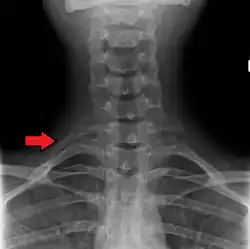

Imagen de rayos X del tórax humano, con las costillas marcadas. -